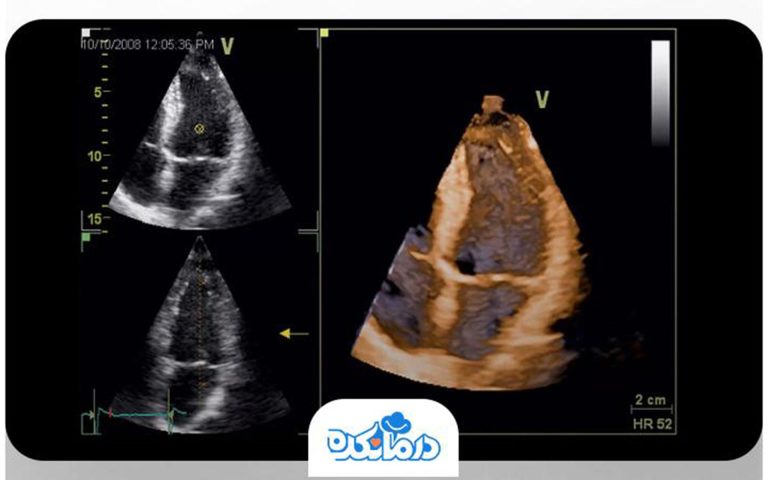

صدها و هزاران پزشک در درمانکده، برای حفظ سلامت شما تلاش میکنند.